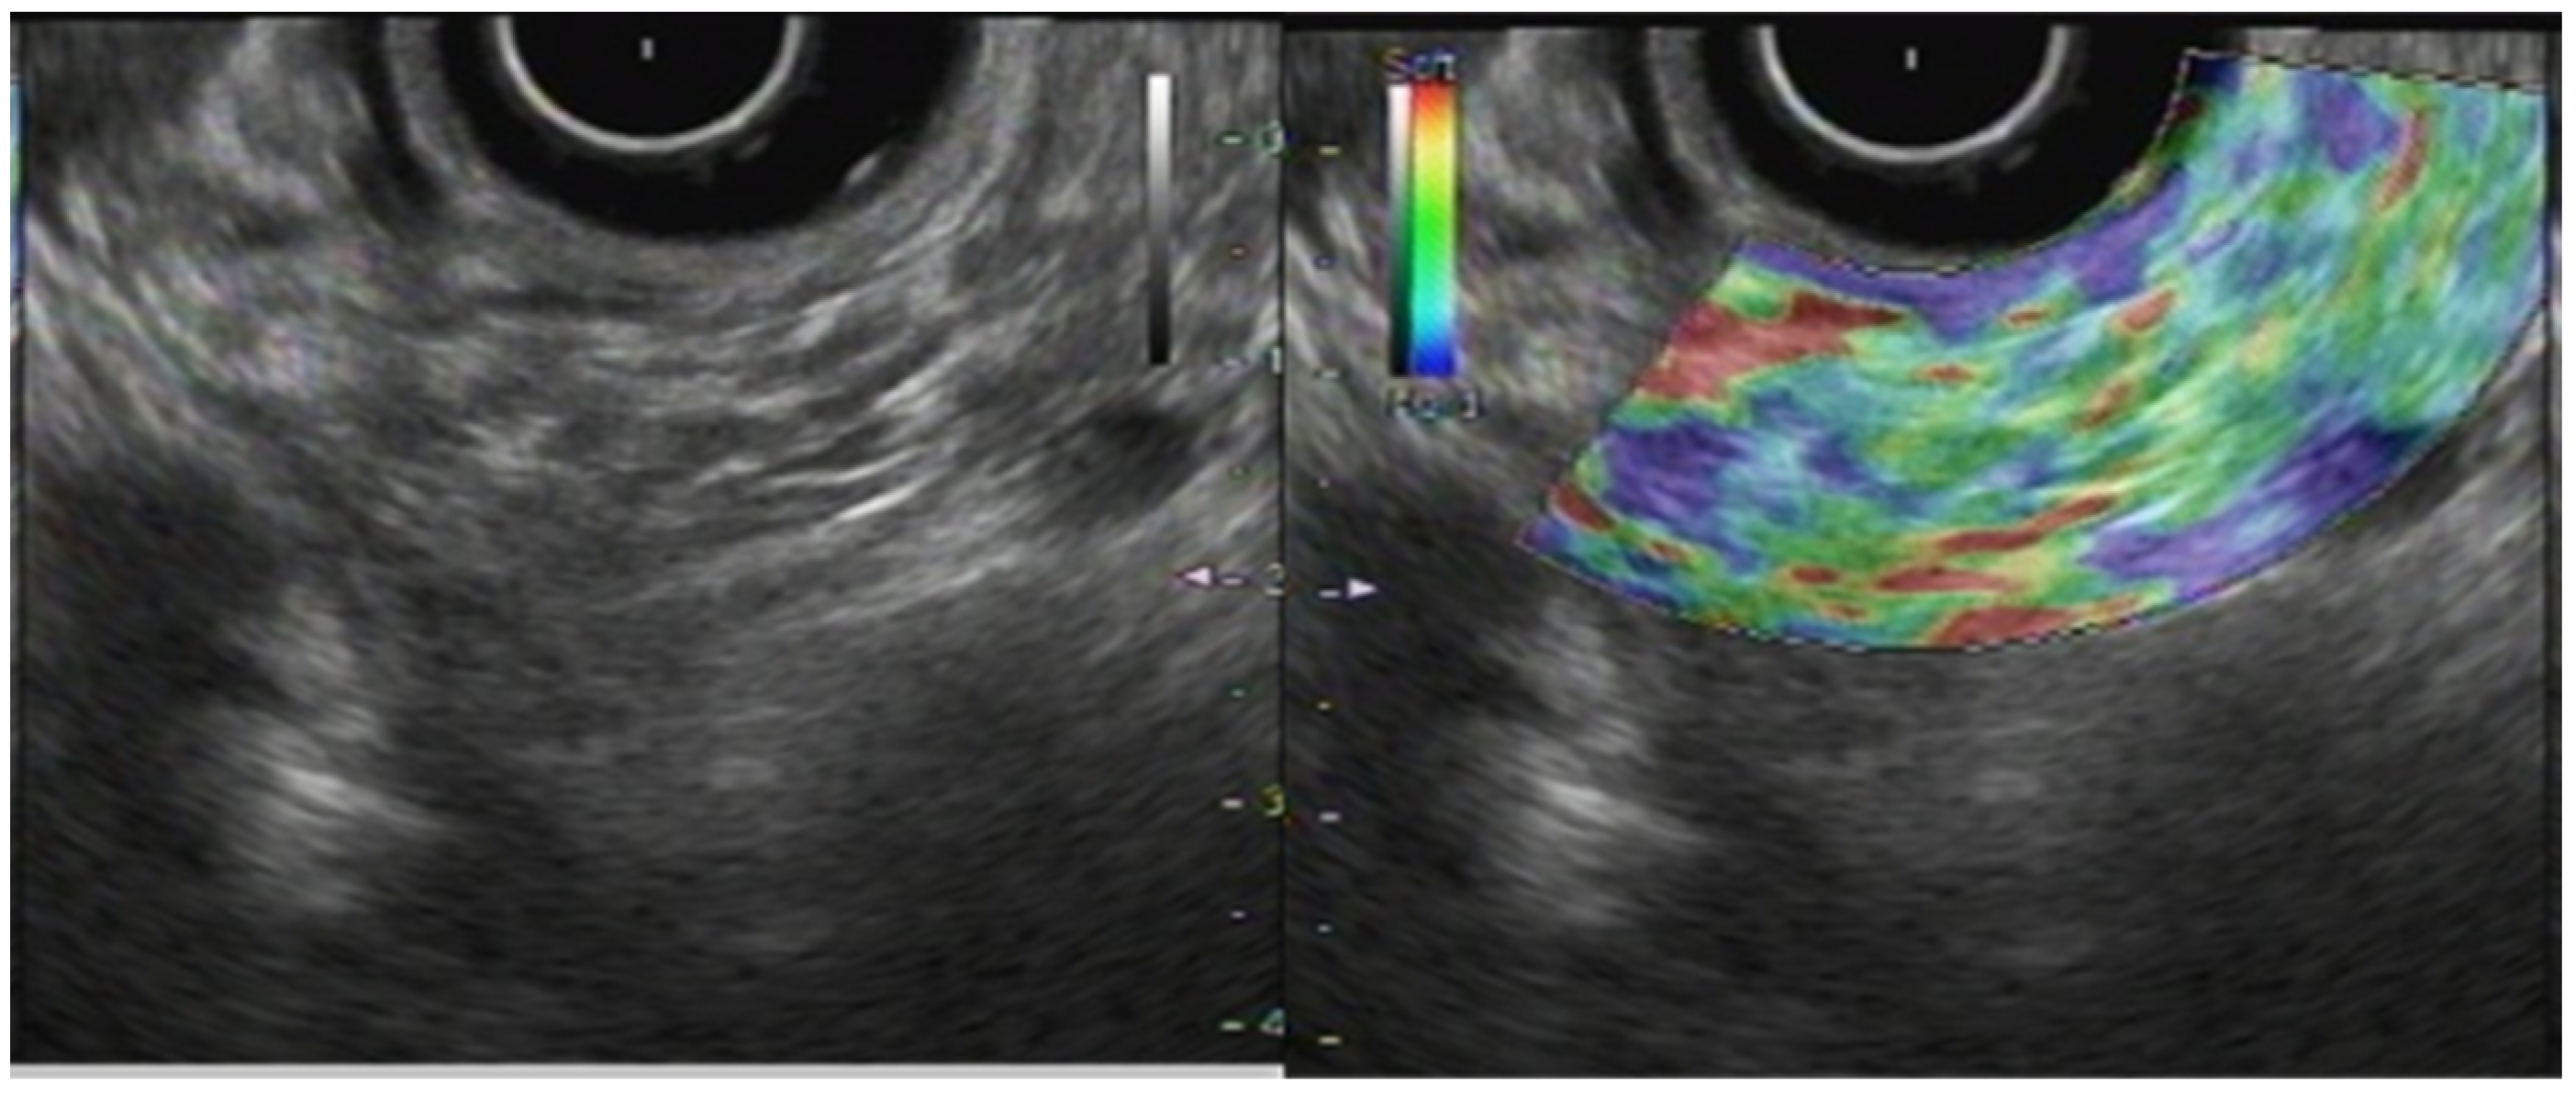

2.3. Shear-Wave Elastography

For SWE, only the quantitative evaluation method is used. Its values are measured as the shear-wave velocity (Vs) and are displayed in meters per second (m/s). After Ohno et al. conducted a clinical study to validate the suitability and usefulness of EUS-SWE, they reported the success rate of pancreatic parenchymal measurement as higher than 96%. The median accuracy of measurement was 74% [17]. For site measurement of pancreatic parenchyma hardness, the error might be caused by compression by the endoscope.